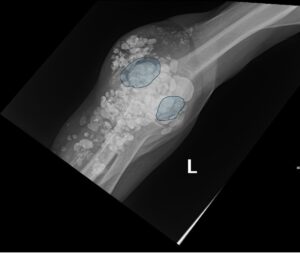

Calcinosis Cutis. Elbow XR, AP, Annotated. JETem 2025

Calcinosis Cutis. Elbow XR AP Annotated. JETem 2025